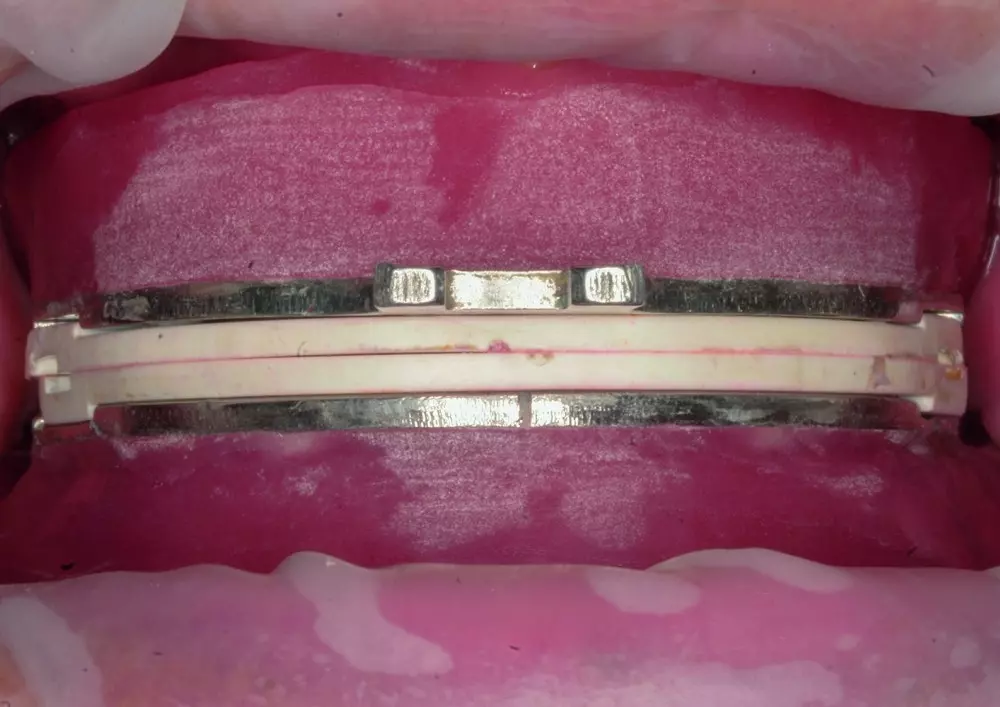

Laser diodowy w ortodoncji znajduje zastosowanie m.in. podczas wprowadzania zatrzymanego kła do łuku zębowego, redukcji bólu po założeniu aparatu ortodontycznego oraz korekty przerostu dziąseł na skutek leczenia aparatem stałym. Dr n. med. Rafał Flieger i dr n. med. Jacek Matys opisują w swoim artykule ww. przypadki, odwołując się do konkretnych przykładów leczenia.